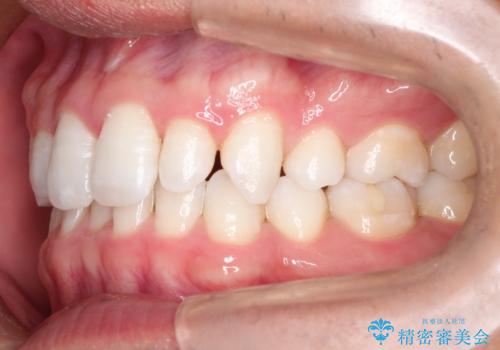

【インビザライン】笑った時の歯並びを綺麗にしたい

- 笑った時の歯の見え方を綺麗にしたいことを主訴に来院されました。

インビザラインにて治療を行なっております。